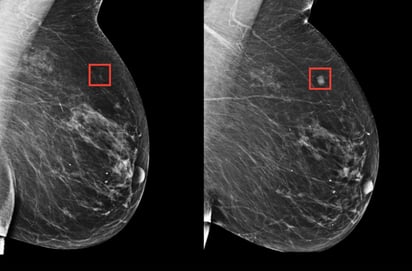

Estudios anteriores estimaban que hasta 30% de los cánceres detectados después de una mamografía negativa ya estaban presentes, pero no fueron identificados en ese momento. Con este antecedente, investigadores y médicos han entrenado sistemas de IA para mejorar la lectura de las imágenes y detectar lesiones difíciles de apreciar.

Aun así, no estaba claro si el uso de IA realmente reduciría los cánceres diagnosticados entre controles. Para aclararlo, el nuevo estudio incluyó a más de 100,000 mujeres en Suecia que fueron asignadas aleatoriamente a dos grupos: uno con mamografías asistidas por IA y otro con el método tradicional, en el que dos radiólogos evaluaban cada imagen. Las pruebas se realizaron entre abril de 2021 y diciembre de 2022.

El sistema de IA empleado había sido entrenado con más de 200,000 estudios previos procedentes de hospitales en más de 10 países. Los resultados mostraron que el 81% de los casos de cáncer en el grupo con IA se detectaron durante el cribado, frente al 74% en el grupo convencional.